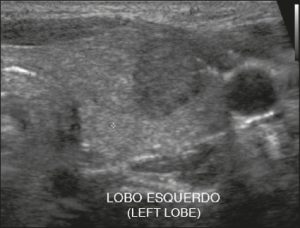

Ở đây, chúng tôi cung cấp các ví dụ minh họa việc áp dụng thực tế hệ thống ACR TI-RADS (Hình 18, 19, 20, 21). Các chú thích dưới hình mô tả chi tiết các mục đã được đánh giá và hiển thị điểm số trong ngoặc đơn.

Hình 20. Hình ảnh nhân giáp hỗn hợp đặc và nang (1 điểm), đồng âm (1 điểm), rộng hơn cao (0 điểm), và lan rộng ra ngoài giới hạn phía trước của tuyến giáp (3 điểm), không có các ổ tăng âm hay bóng lưng (0 điểm). Do đó, tổng điểm là 5 điểm và mức độ nguy cơ được phân loại là TR4.